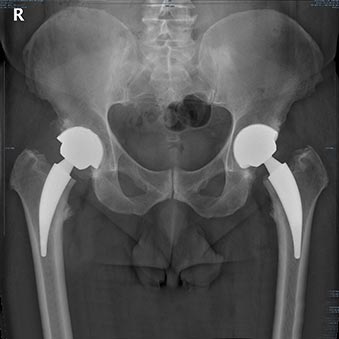

O mundo da ortopedia prepara-se para mais uma edição do 3.º HIP G.I.N. (Global Issue Network) Summit, um evento dedicado às grandes questões da cirurgia da anca. Organizado pelo Lusíadas Knowledge Center em parceria com a UpHill Events, o summit ocorrerá nos dias 21 e 22 de novembro de 2025, na Herdade da Comporta, reunindo…